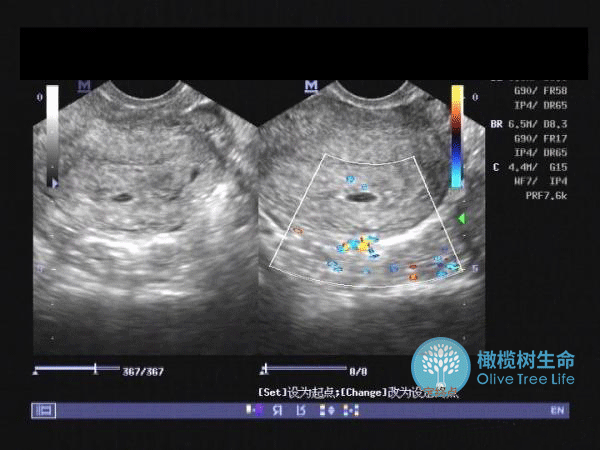

那我们如何查看自己的“余额”?怎么判断卵巢是否健康?别担心,橄榄树生命小橄榄今天就来告诉你!

查看“家底”和判断卵巢健康的指标